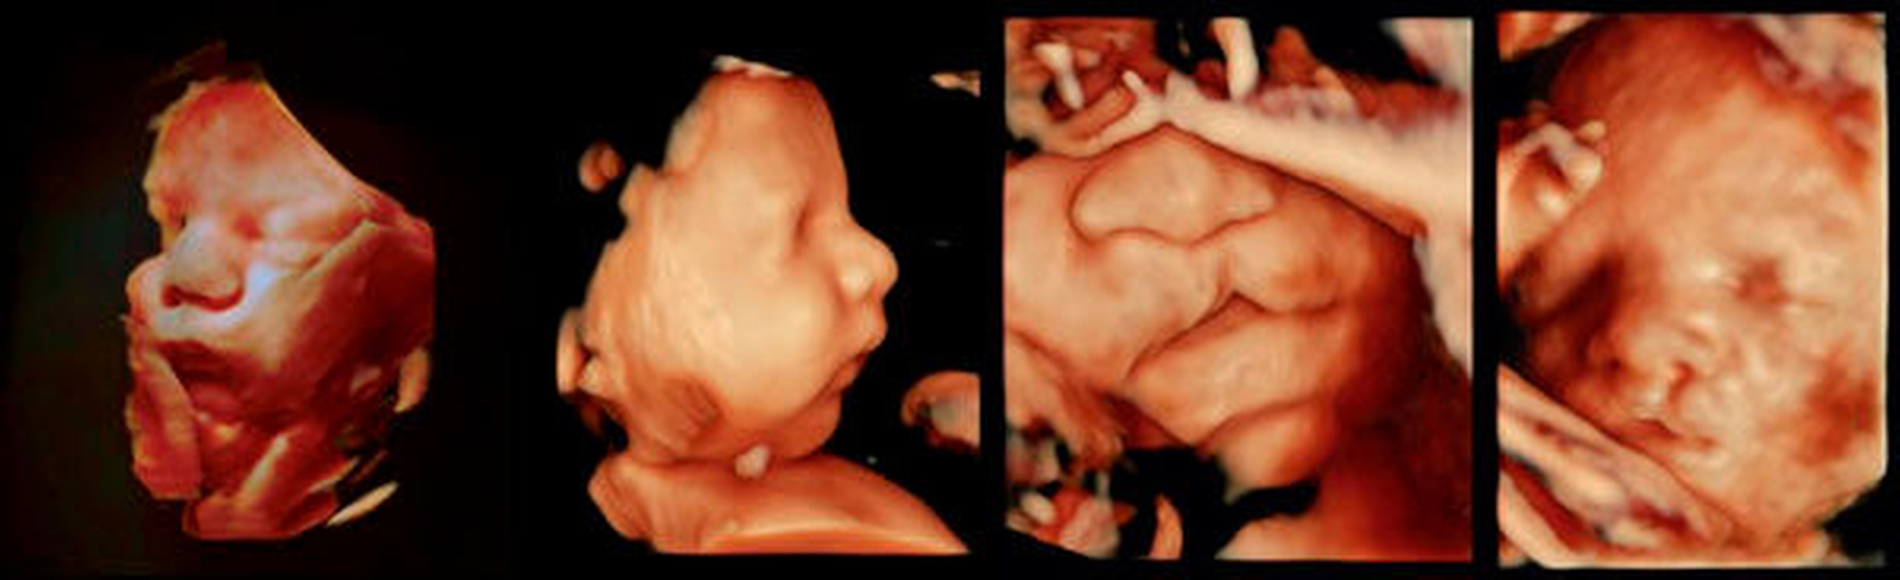

Die Pränataldiagnostik erlaubt etwa ab der 12. Schwangerschaftswoche eine frühzeitige Diagnostik von Lippenspalten. Gaumenspalten sind schwerer darstellbar und können daher meist erst später diagnostiziert werden. Moderne Geräte erlauben dreidimensionale Rekonstruktionen von intrauterinen fetalen Ultraschallbildern, mit denen auch eine Unterkiefer-Rücklage festgestellt werden kann (Abbildung 2). Die frühe Diagnosesicherung ermöglicht eine adäquate Beratung der Eltern über die zu erwartende Behandlung und über die Planung der Geburt und der unmittelbar postnatalen Versorgung.